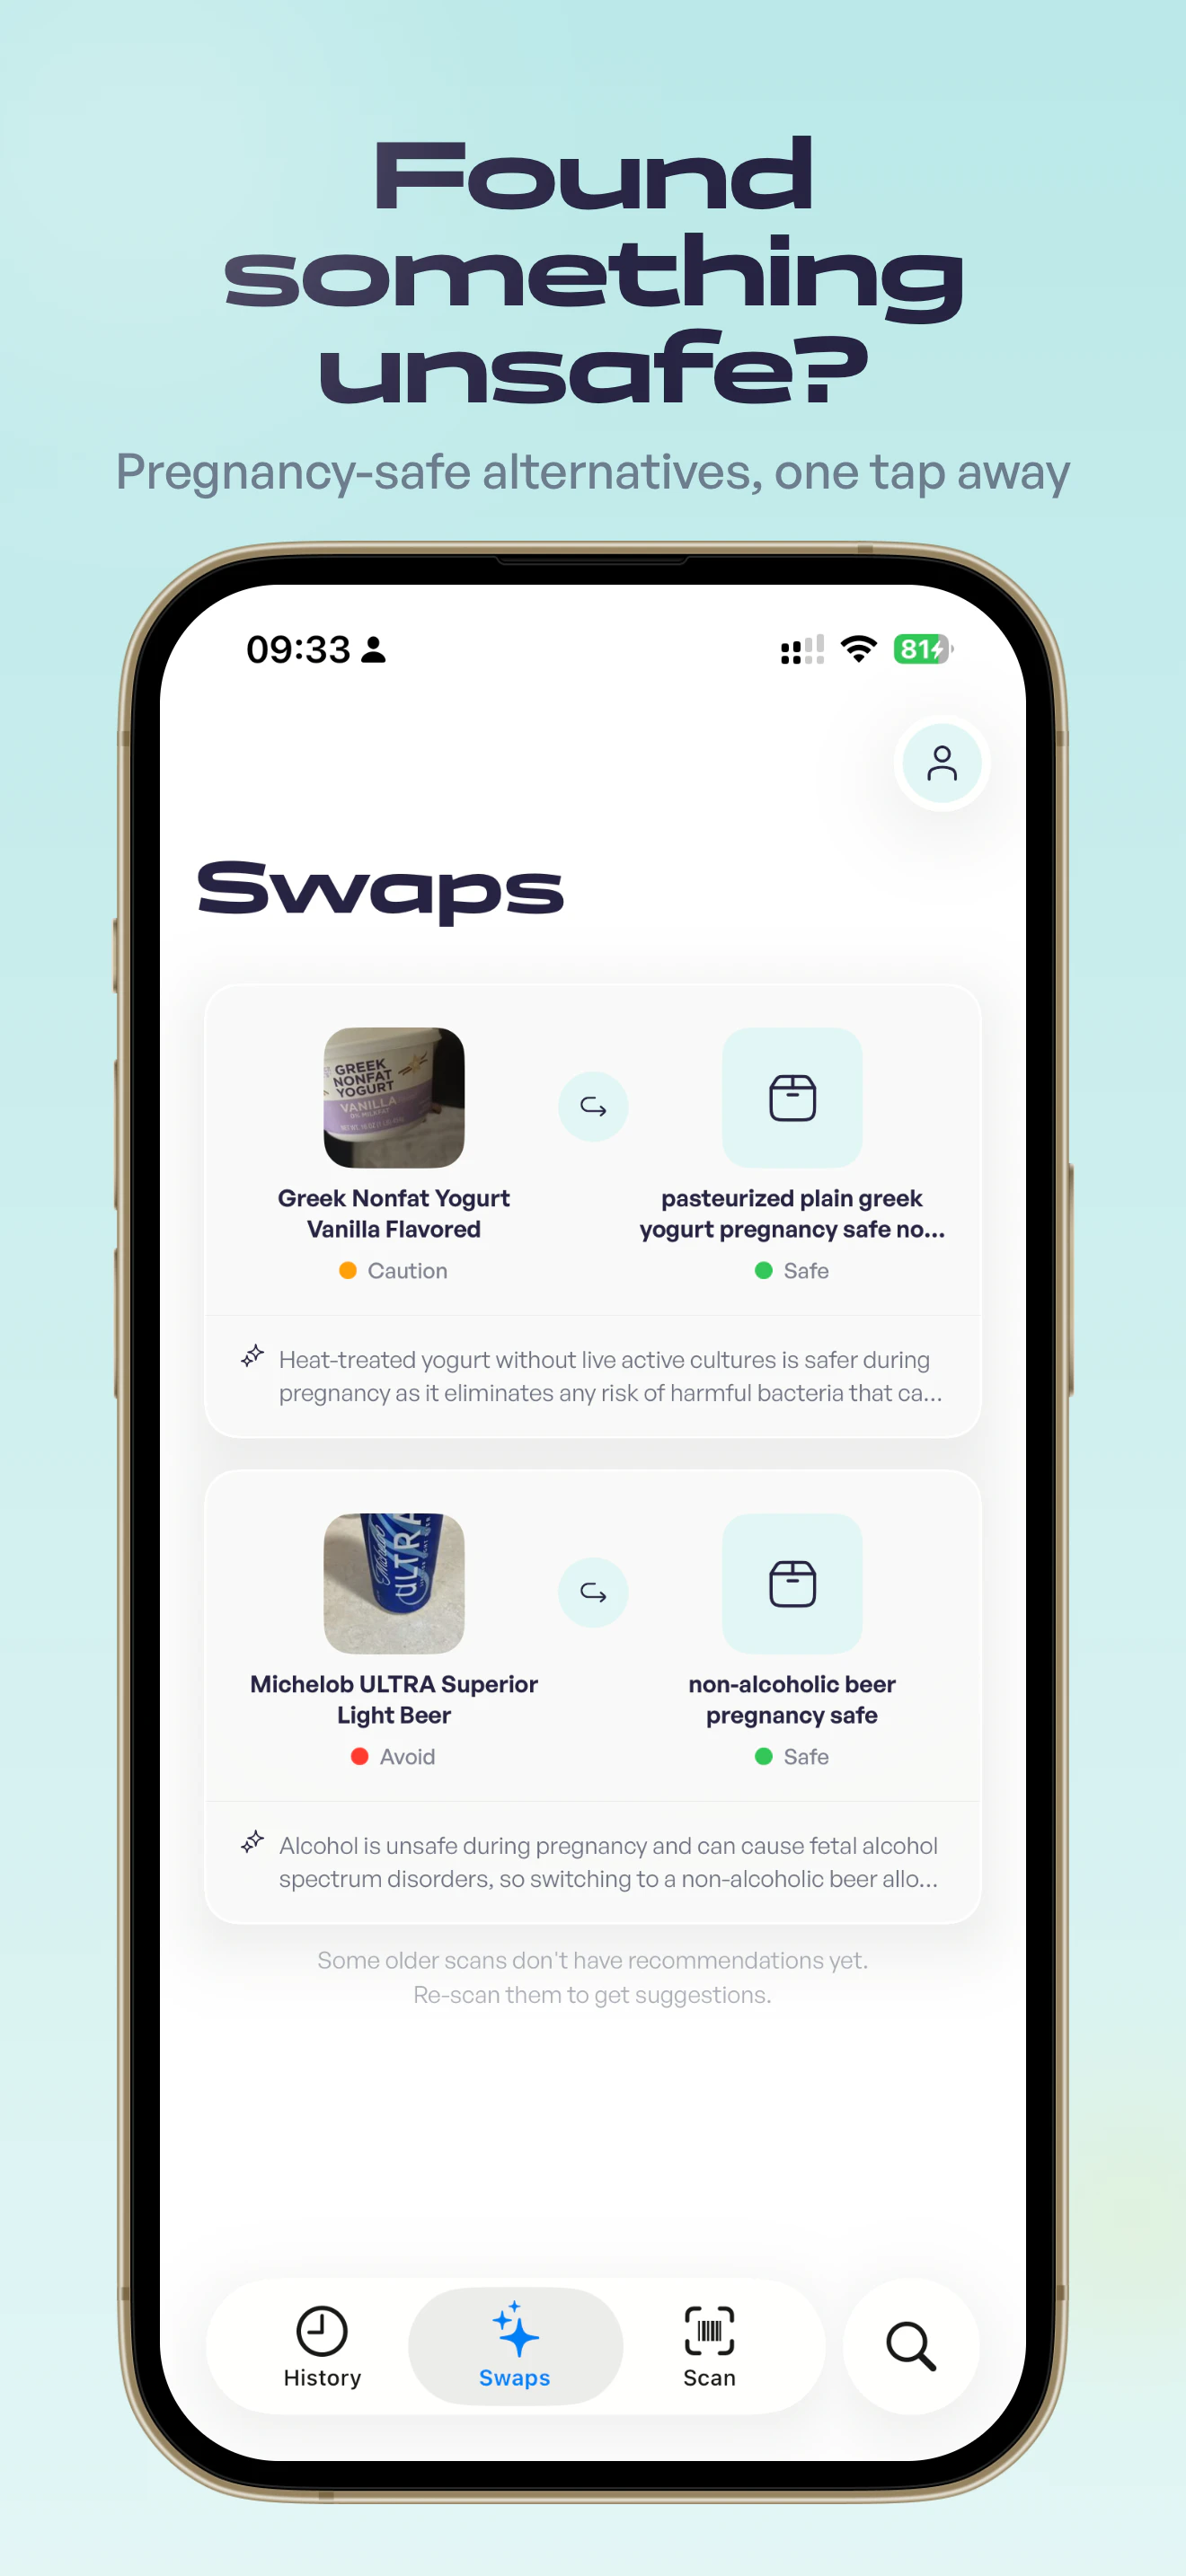

Scan any product to know it's safe during pregnancy

Oli is a pregnancy safety scanner. Scan a barcode, search by name, or photograph an ingredient la...